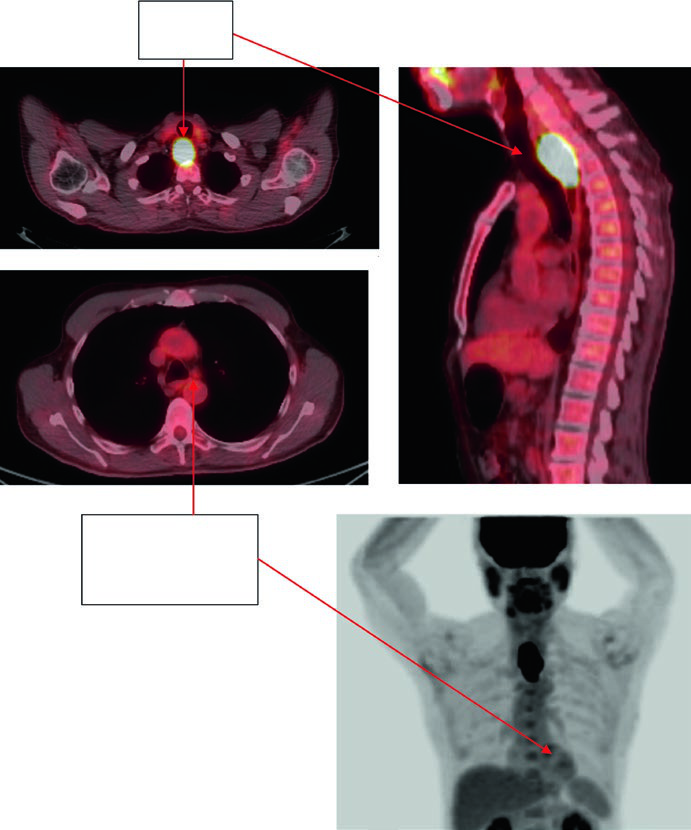

Case 1: Cervical/Upper Thoracic SCC — 69-Year-Old

A 69-year-old patient with SCC of the cervical/upper thoracic esophagus. PET-CT revealed FDG-avid primary and mildly avid paratracheal lymph nodes. EGD showed an ulcerating submucosal mass 15–23 cm from the incisors. Delineated volumes included: brachial plexus (purple), larynx (yellow), esophageal GTV (red), nodal GTV (green), CTV (orange), PTV 54 Gy (cyan), and PTV 60 Gy (dark blue). The superior border of the supraclavicular field was placed at the inferior border of the cricoid cartilage, with bilateral elective SCV nodal coverage.